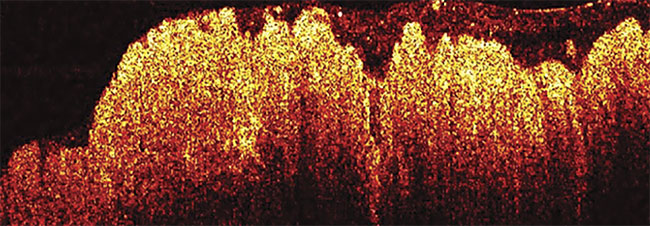

Veterinarians Use OCT to Evaluate Eye Health, Cancer Margins, and Joint Strength

Medical doctors have long understood the value of optical coherence tomography (OCT) for monitoring human health. Veterinarians are learning that the technology can be just as vital in evaluating the well-being of patients in the animal kingdom. Often used in conjunction with other technologies, OCT has the capacity to map out tissue at high resolution as a reference point for further experiments and treatments.